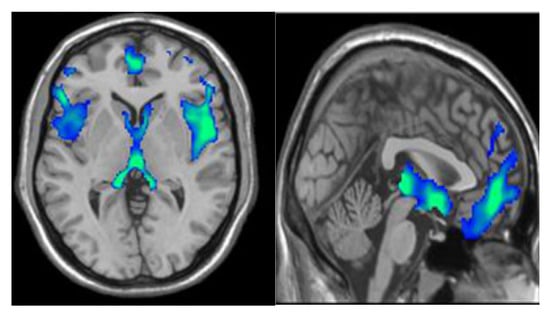

The original density f ( x ) with the feature space is initially utilized for identifying the modes of density. The gradient f ( x ) = 0 is used for locating the modes that establish zeros for the mean shift process. The gradient estimation of the density attained the estimator of gradient that employed the function linearly. In the next phase, feature extraction is carried out from the segmented tissues (AD, NC, MCI, EMCI, LMCI, and SMC) in the resting state fMRI image. The segmentation output of the SAS method is represented in Figure 3.

Figure 3. Segmentation output of the SAS method.